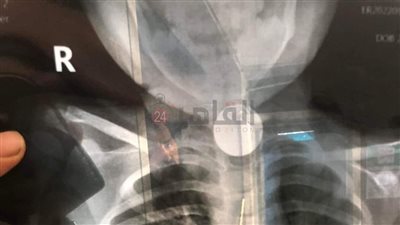

عمرة 10 أشهر.. فريق طبي بـ«مجمع الأقصر الطبي» ينقذ حياة رضيع ابتلع بطارية لعبة